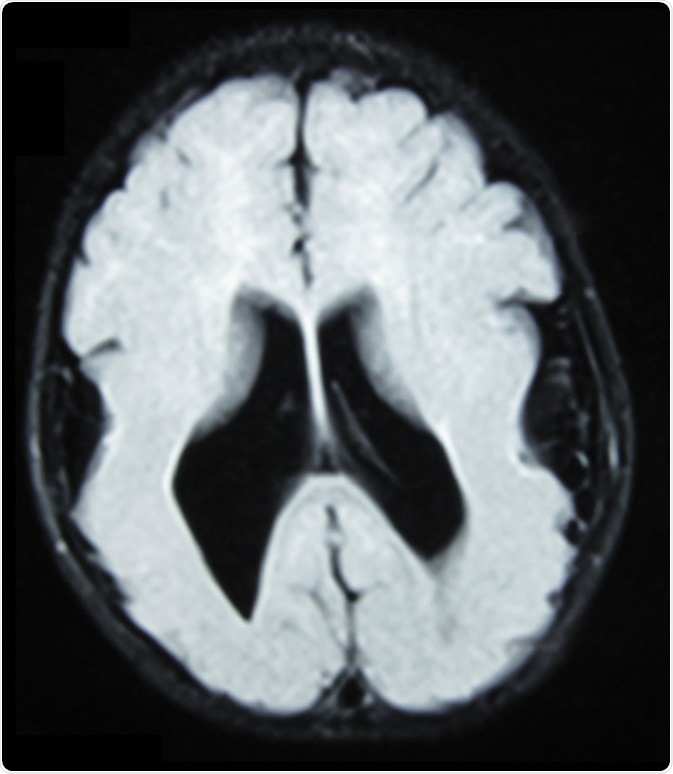

Brain MRI, T1 weighted, transverse plane, that shows lissencephaly, manifested as scarce and wide circumvolutions, mostly in the occipital, parietal, and temporal lobes. As aggregated findings, there is ventriculomegaly, no true Sylvian cissure, too thick gray matter and ectopic gray matter in the white matter. Image Credit: Ralphelg, https://creativecommons.org/licenses/by-sa/3.0/deed.en